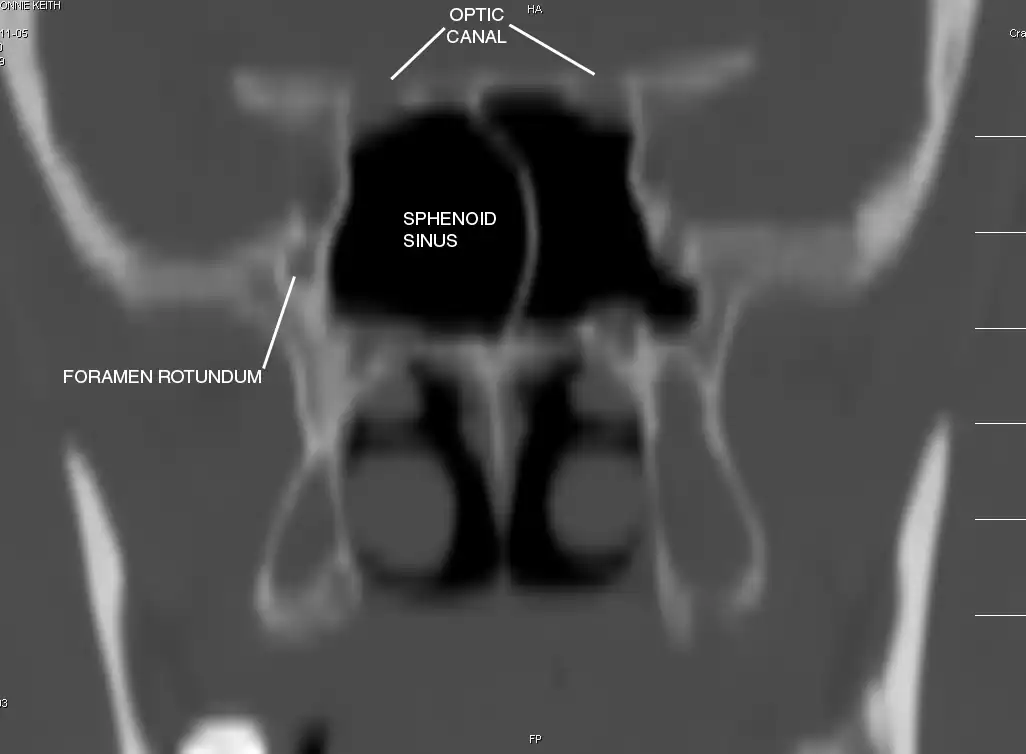

Sphenoid Sinus has 12 close structures: II, III, IV, V1, V2, VI, Vidian Nerve, Carotid artery, Brain, Dura, Pituitary.

Pertinent Sinonasal Anatomy

- II = Optic Nerve: 25-50% with bony dehiscence into sphenoid sinus.

- V2 = Maxillary division, Trigeminal Nerve: exits foramen rotundum, superomedial to V3's foramen ovale.

- C = Carotid Artery: often with bony dehiscence into sphenoid. Together with CN II forms opticocarotid recess.